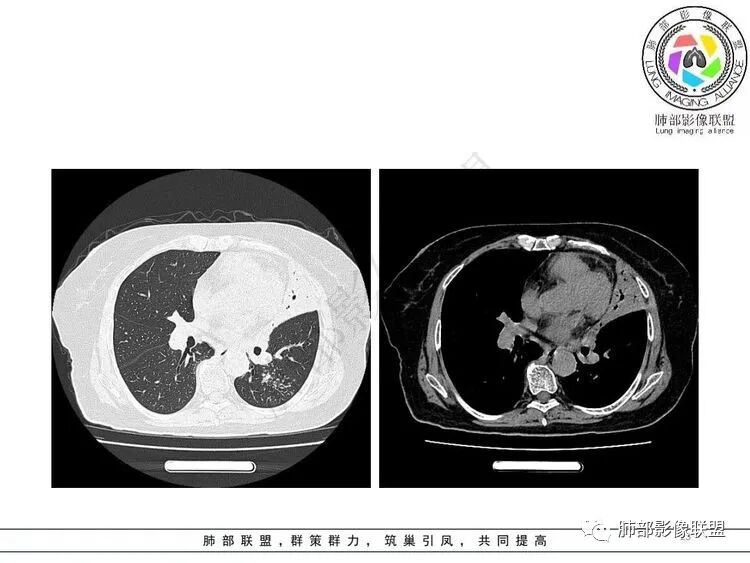

2.纵隔左移。肺动脉增宽。

2.“胸闷、气促”以及呼衰的临床表现,难以以当前肺部的病灶加以解释。

D-二聚体升高,肺动脉成像等明确患者肺栓塞的存在!

影像特点支持结核。气促、左上肺病灶似乎不能解释I型呼吸衰竭加上D—二聚体明显升高、肺动脉干增粗,临床需要想到二元可能:肺结核合并肺栓塞可能,需要完善CTPA明确有没有肺栓塞,因为急性肺栓塞是急危重症。